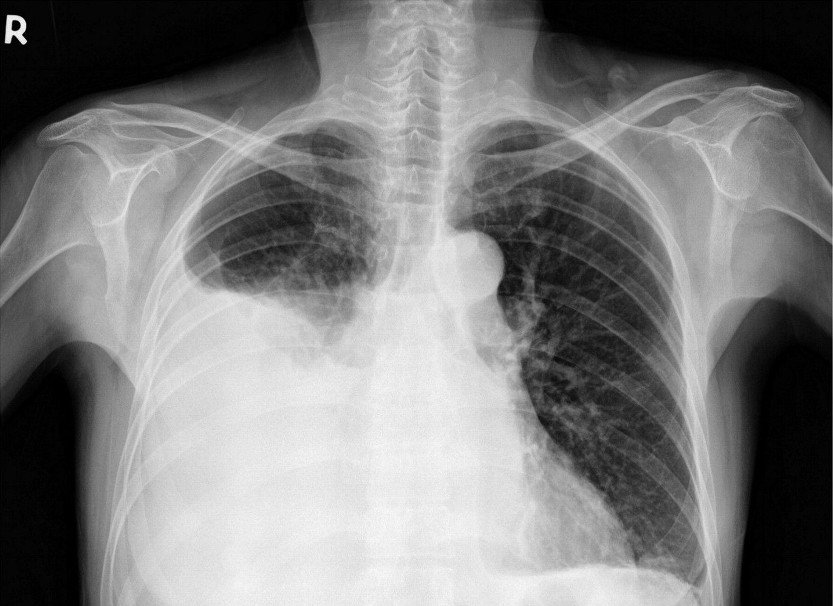

Если имеются признаки плеврита, врач назначает следующие исследования:

рентген органов грудной клетки;

- УЗИ грудной клетки;

- КТ – определяет причину болезни;

- пункция из полости плевры – производится забор жидкости, которая отправляется на гистологическое и цитологическое исследование.